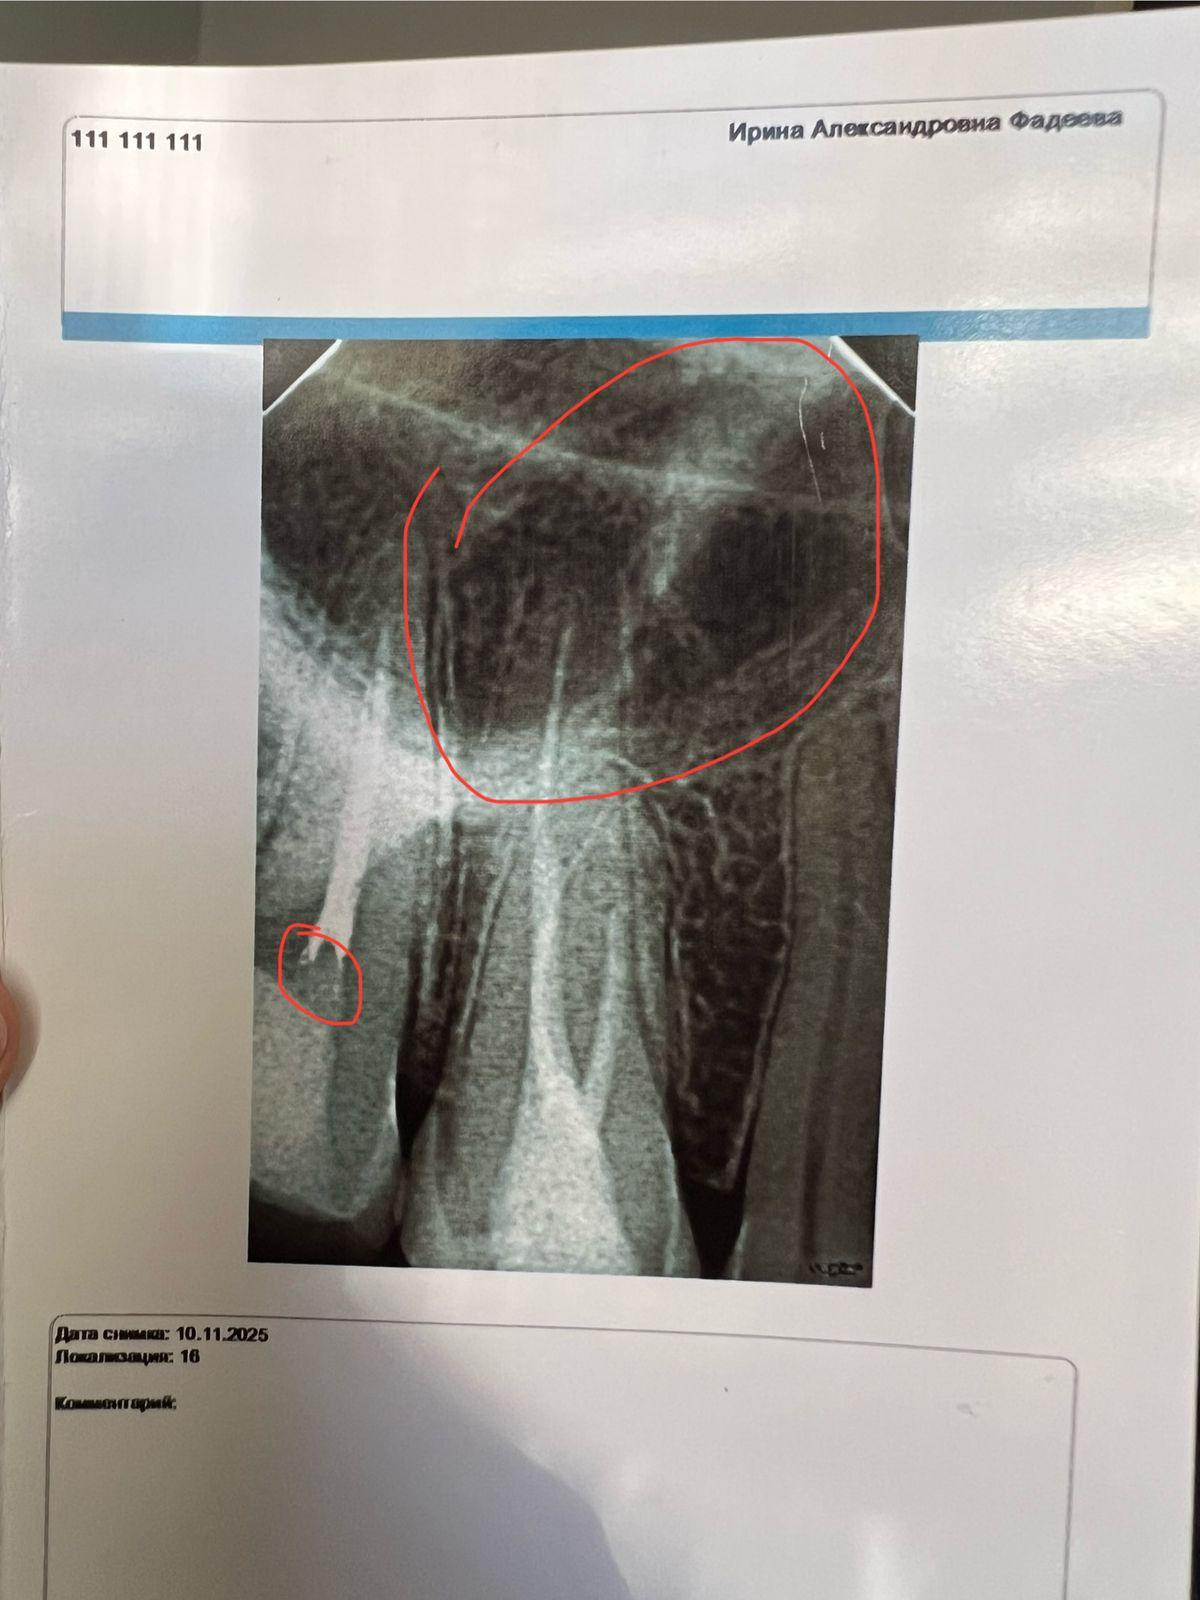

Здравствуйте, часто 15 зуб ноет, 1,5 года назад был вылечен ,удаляли нервы и запломбировали , на снимке где маленький кружок это пустота или пломба? И что это за потемнение на вверху где 16 зуб , была на приеме 10.11, сказали визуально зубы здоровые .И второй снимок 36 зуб , можно его вылечить без удаление нервов ?

Добрый день! По поводу 15 зуба: нужно сделать КТ исследование, посмотреть качество пломбировки, так же, оценить качество пломбы. Потому, как переодически болеть может из за попадания и застревания пищи между зубами.